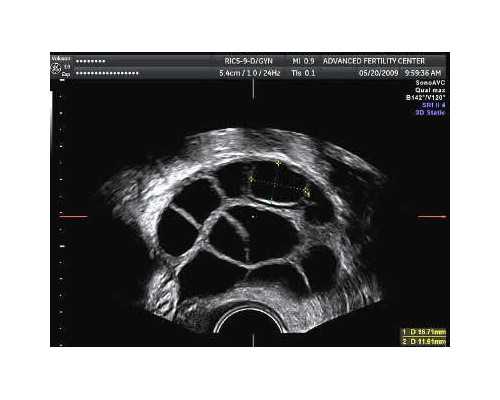

1、一定要确保宝妈怀孕的时间已经达到了胚芽的长度达到了10mm或者10mm以上,因为这是做检测的硬性条件。宝妈要在当地的医院进行B超检测,并且要求B超单上有标注宝妈的胚芽长度达到了10mm,即已经满足做检测的条件。

验血鉴定胎儿性别的原理其实就是因为宝妈的外周血中含有宝宝的基因片段,通过筛查这种片段是否含有Y基因,确定是否含有Y染色体。我们都知道关于男性和女性的染色体虽都是23对,46条,但是它们是有区别的。因为男性的第23对性染色体是XY,而女性的则是XX.我们都知道,孩子的性别是和性染色体息息相关的,孩子含有Y染色体即为男孩,不含有则为女孩。

因此医疗人员通过血液中的DNA片段确定是否含有Y染色体,进而就能确定宝宝的性别了。通常这种检测的准确性能达到99.8%之高,所以各位宝妈大可放心。